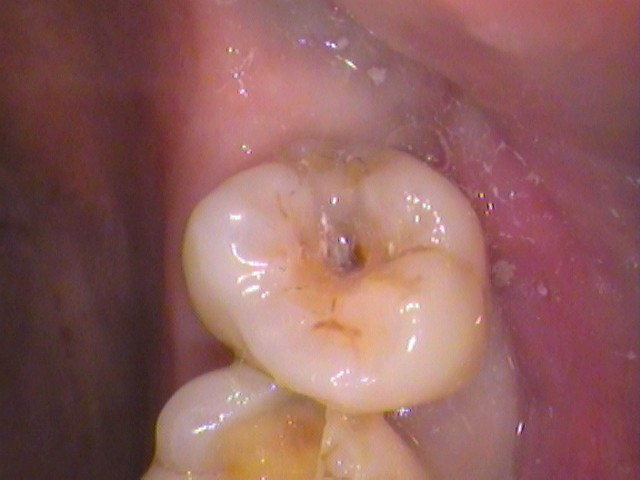

・歯の溝からの虫歯

歯の窪みの中心に茶色い虫歯が侵入している。

歯と歯の間から、また歯の外側の溝から虫歯汚れが入り込んできている。